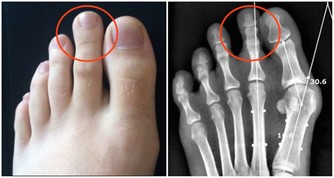

• 骨質疏鬆:長期飽食易使骨骼過分脫鈣,患骨質疏鬆的概率會大大提高。